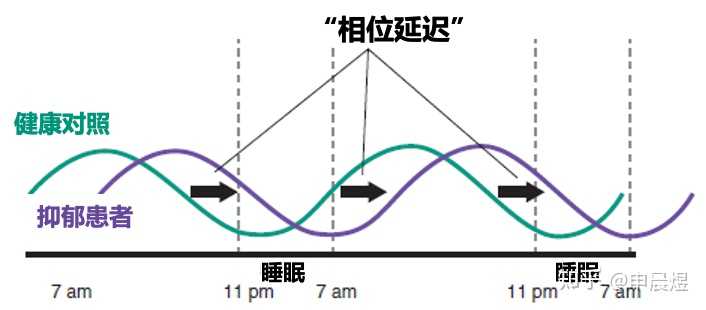

抑郁症可致生物节律相位延迟

抑郁患者的生物节律往往是相位延迟的,意味着早上觉醒度不足,晚上入睡困难。难以入睡进一步加剧了白天的困倦感[7]。